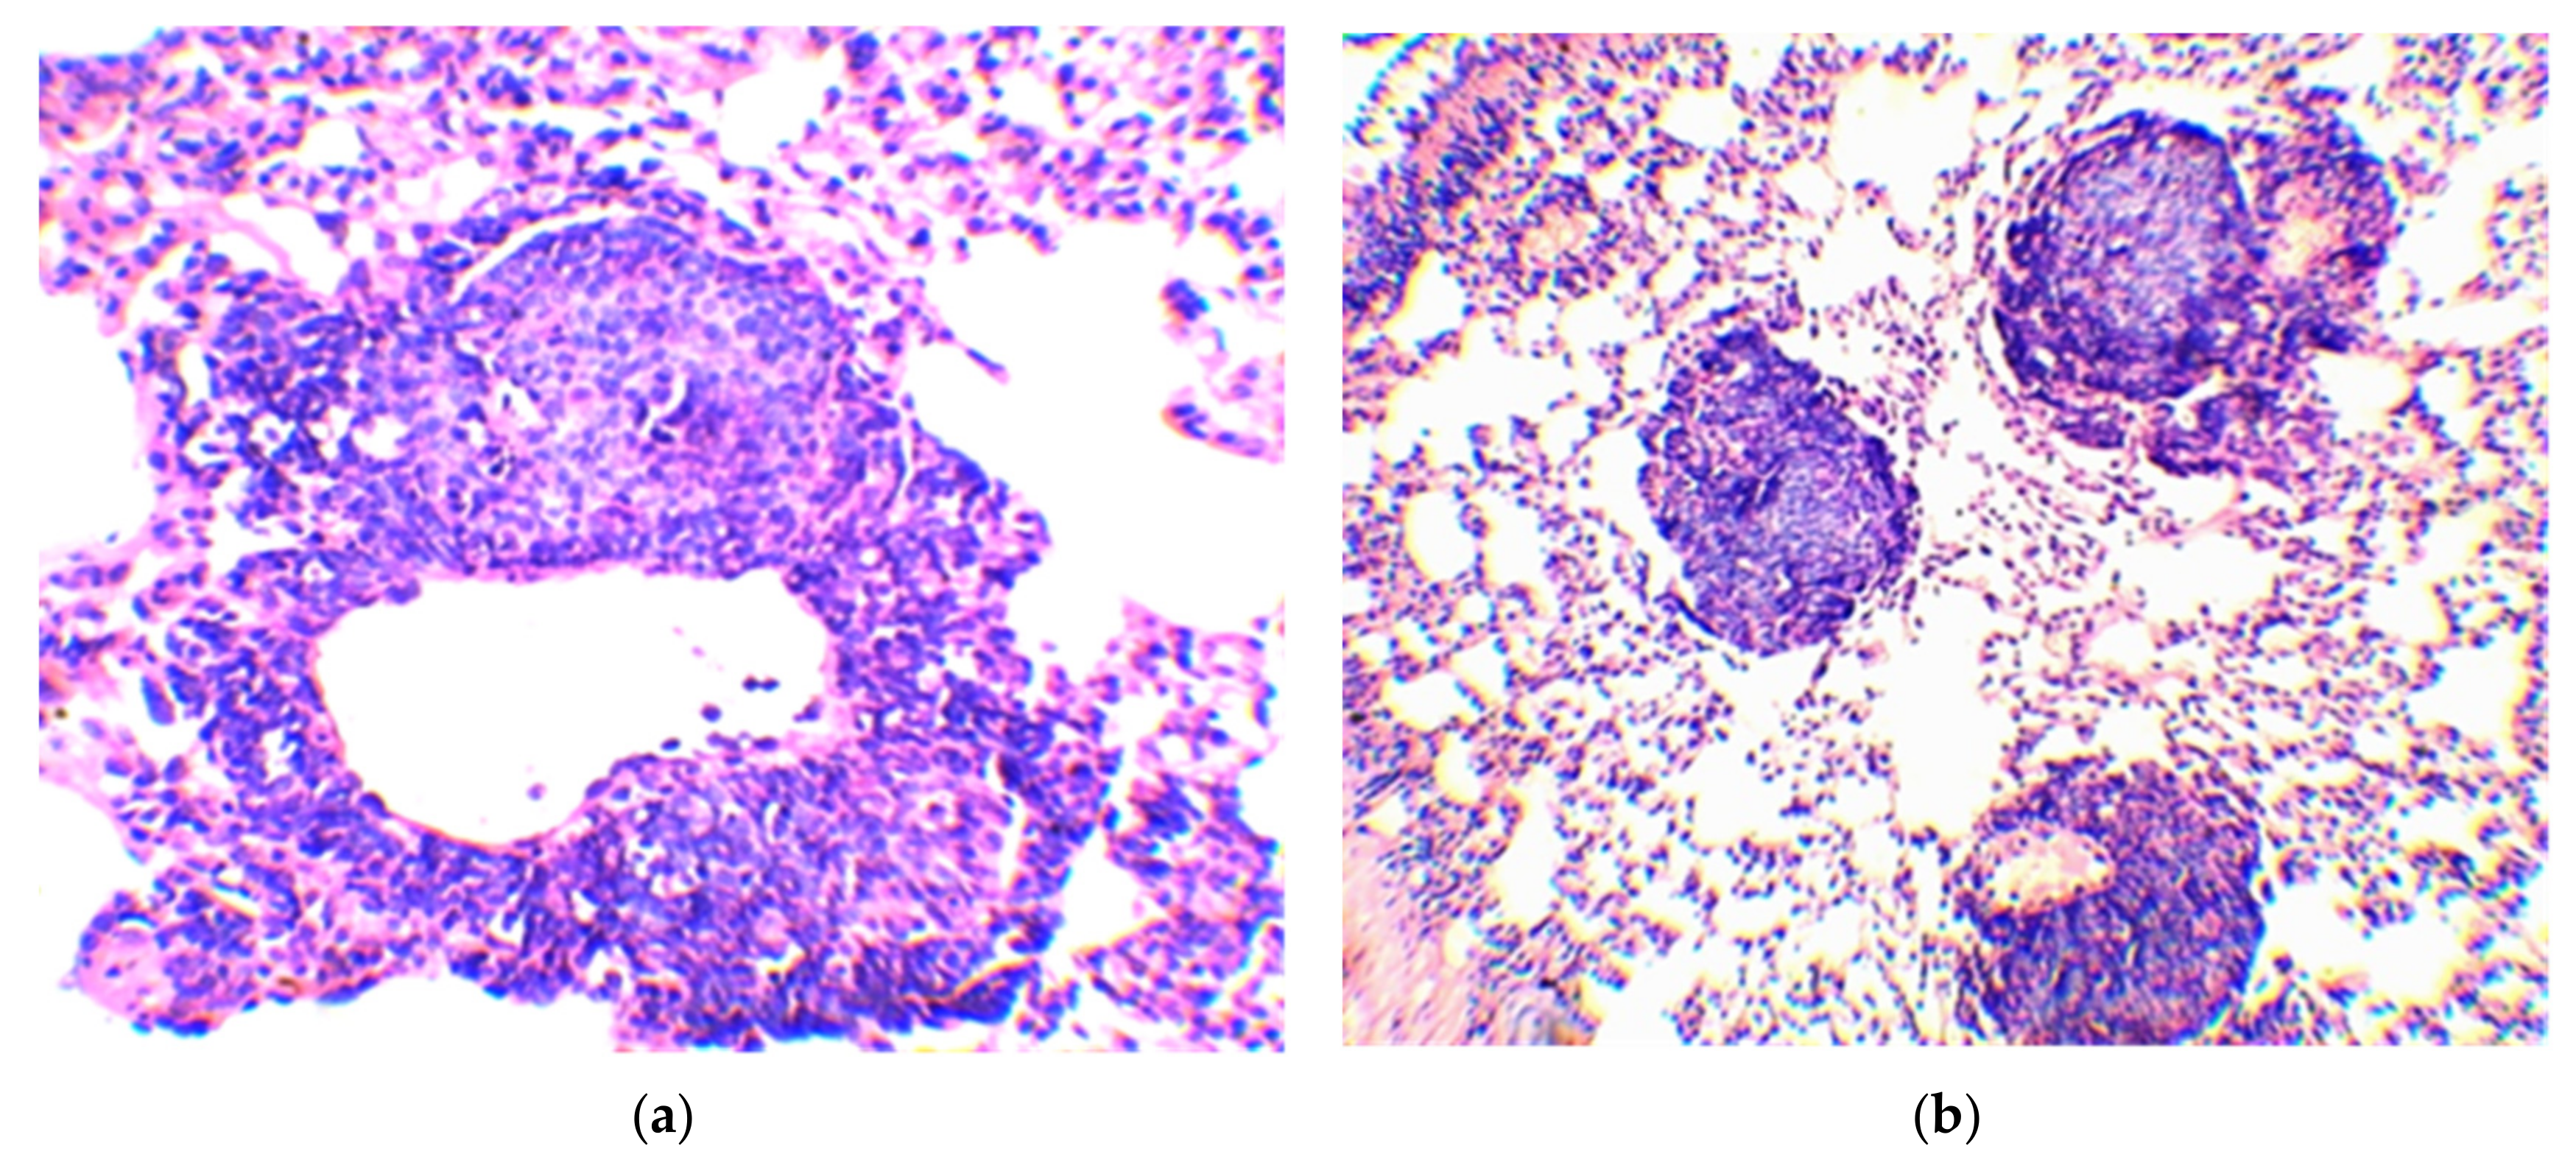

| Group No. | BCG Vaccine | Compound | Mean Follicle Area (µm2) | Mean Follicle Diameter (µm) | Follicle Size Distribution by Diameter (µm) | Number of Follicles of the Same Size (%) |

|---|---|---|---|---|---|---|

| 1 | − | − | 34,103.0 ± 2766.5 | 203.0 ± 8.8 | 70–100 | 3.3 |

| 110–160 | 23.3 | |||||

| 170–220 | 40.0 | |||||

| 230–270 | 26.7 | |||||

| 280–300 | 6.7 | |||||

| 2 | + | Betulinic acid | 37,478.8 ± 4532.1 | 216.3 ± 14.0 | 70–100 | 6.7 |

| 110–160 | 16.7 | |||||

| 170–220 | 33.3 | |||||

| 230–270 | 25.7 | |||||

| 280–300 | 16.7 | |||||

| 3 | + | Betulin | 19,080.7 ± 1905.0 1 | 147.0 ± 9.0 2 | 70–100 | 10.0 |

| 110–160 | 53.5 | |||||

| 170–220 | 36.7 | |||||

| 4 | + | Betulonic acid | 11,458.4 ± 1240.7 2 | 115.7 ± 6.5 2 | 70–100 | 43.3 |

| 110–160 | 46.7 | |||||

| 170–190 | 10.0 | |||||

| 5 | + | − | 20,742.3 ± 2386.4 1 | 155.0 ± 9.1 2 | 70–100 | 13.3 |

| 110–160 | 50.0 | |||||

| 170–220 | 23.4 | |||||

| 230–250 | 13.3 |